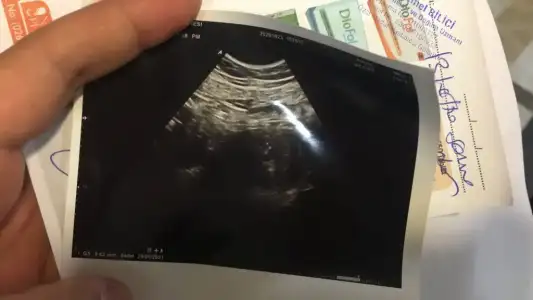

Merhaba kizlar, cok şükür 1 yil sonra yeniden hamile kaldim  Bugun doktora gittim 5,3 haftalik dedi, karından Hsg ile kese göründü fakat kalp atışı duyulmadi 2 hafta sonra gelin kalp atışını dinleyelim insallah dedi. İlk bebegimin kalp atışını duymamamıştık

Bugun doktora gittim 5,3 haftalik dedi, karından Hsg ile kese göründü fakat kalp atışı duyulmadi 2 hafta sonra gelin kalp atışını dinleyelim insallah dedi. İlk bebegimin kalp atışını duymamamıştık  yine aynısının olmasindan cok korkuyorum

lutfen fikirlerinizi paylasabilir misiniz ? Ekde minik patatesimin bugünki görüntüsü var, 9,4mm yazıyor insallah normaldir hersey dua edin lutfen

lutfen fikirlerinizi paylasabilir misiniz ? Ekde minik patatesimin bugünki görüntüsü var, 9,4mm yazıyor insallah normaldir hersey dua edin lutfen